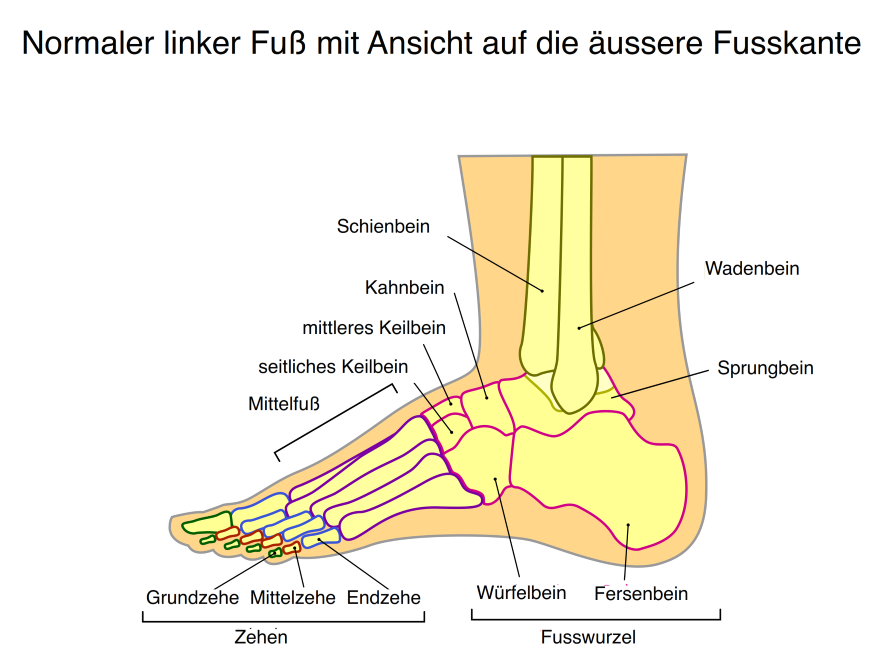

Fußanatomie: Lerne Deine Füße Kennen! – GetSteps

Fuß Füße Sprunggelenk Zehen Arztpraxis Lüneburg Dr. Med. Thomas Hartmann